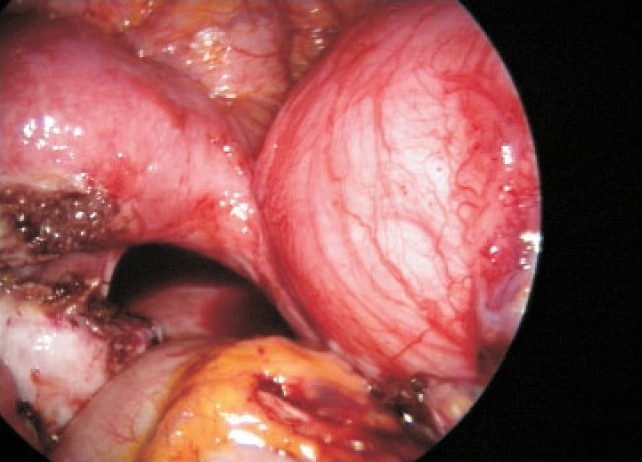

未婚女孩重度痛经,因双侧子宫内膜瘤剖腹手术,经达那唑和GnRHa Depo注射治疗三年多。腹腔镜检查发现她有一个大的、不相通的、功能不全的角伴同侧肾发育不全。腹腔镜下对原始角的切除使疑似子宫内膜异位瘤得到了很大的缓解,这并不是她剧烈疼痛的原因。

An unmarried girl with severe dysmenorrhea had laparotomy for bilateral endometriomas, later treated with danazol and GnRHa Depo injection for more than three years. On laparoscopy she had a large, noncommunicating, functioning rudimentary horn with ipsilateral renal agenesis. Laparoscopic excision of the rudimentary horn gave major relief from the suspected endometrioma, which was not the cause of her severe pain.